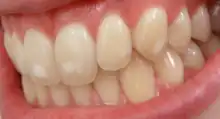

Dental fluorosis appears as a range of visual changes in enamel[4] causing degrees of intrinsic tooth discoloration, and, in some cases, physical damage to the teeth. The severity of the condition is dependent on the dose, duration, and age of the individual during the exposure.[1] The "very mild" (and most common) form of fluorosis, is characterized by small, opaque, "paper white" areas scattered irregularly over the tooth, covering less than 25% of the tooth surface. In the "mild" form of the disease, these mottled patches can involve up to half of the surface area of the teeth. When fluorosis is moderate, all of the surfaces of the teeth are mottled and teeth may be ground down and brown stains frequently "disfigure" the teeth. Severe fluorosis is characterized by brown discoloration and discrete or confluent pitting; brown stains are widespread and teeth often present a corroded-looking appearance.[1]

The adequate diagnosis of fluorosis can be diagnosed by visual clinical examination. This requires inspection of dry and clean tooth surfaces under a good lighting.[6] There are individual variations in clinical fluorosis manifestation which are highly dependent on the duration, timing, and dosage of fluoride exposure. There are different classifications to diagnose the severity based on the appearances. The clinical manifestation of mild dental fluorosis is mostly characterised a snow flaking appearance that lack a clear border, opaque, white spots, narrow white lines following the perikymata or patches as the opacities may coalesce with an intact, hard and smooth enamel surface on most of the teeth.[7] With increasing severity, the subsurface enamel, all along the tooth becomes more porous. Enamel may appear yellow/brown with discolouration and/or many pitted white-brown lesions similar to cavities. They are often described as "mottled teeth".[8] Fluorosis does not cause discolouration to the enamel directly, as upon eruption into the mouth, affected permanent teeth are not discoloured yet. In dental enamel, fluorosis causes subsurface porosity or hypomineralizations, which extend toward the dentinal-enamel junction as the condition progresses and the affected teeth become more susceptible to staining. Due to diffusion of exogenous ions (e.g., iron and copper), stains develop into the increasingly and abnormally porous enamel.[7]